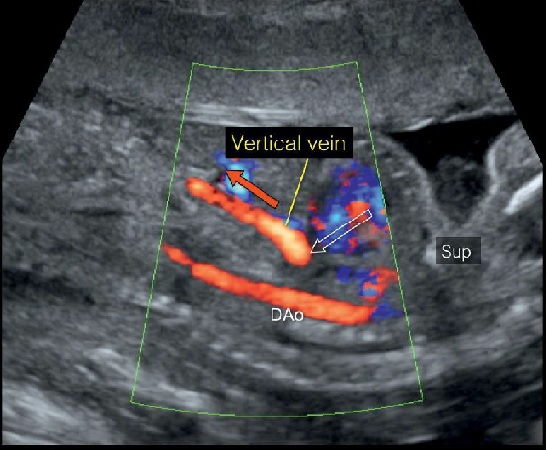

Thể dưới tim (type III - Infracardiac)Trong thể này cả 4 tĩnh mạch phổi đổ về tĩnh mạch hợp lưu phía sau tâm nhĩ (Hình 1D), hợp lưu này nối với một tĩnh mạch dọc xuống bất thường, tĩnh mạch dọc xuống này đi cùng với thực quản qua lỗ thực quản của cơ hoành rồi đổ vào hệ thống tĩnh mạch cửa. Điểm gặp nhau giữa tĩnh mạch cửa với tĩnh mạch dọc xuống sẽ rất khó nhận biết nếu siêu âm 2D thông thường. Siêu âm Doppler màu trên mặt cắt dọc sẽ thấy một mạch máu nhỏ vượt qua cơ hoành vào gan hướng dòng chảy từ trên xuống dưới (Hình 15), Doppler màu cho biết chiều của dòng chảy cùng chiều với động mạch chủ xuống, Doppler phổ sẽ cho phổ tĩnh mạch. Thể dưới tim thường thấy ở thai nhi có kiểu hình bên phải (right isomerism).

Hình 15: Thai nhi TAPVR thể dưới tim. Mặt cắt chẩn đoán tối ưu là mặt cắt dọc ngực bụng, dùng Doppler màu, ta thấy động mạch chủ xuống (DAo) nằm phía sau, song song phía trước động mạch chủ bụng là một mạch máu (mũi tên đỏ) có nguồn gốc từ ngực chạy vào gan. Mạch máu này chính là tĩnh mạch dọc xuống (vertical descending vein), cùng chiều dòng chảy với động mạch chủ xuống do vậy có cùng màu trên hình ảnh Doppler màu. Vị trí xuất phát của tĩnh mạch dọc xuống (vertical descending vein) là ở phía sau tim (mũi tên rỗng).